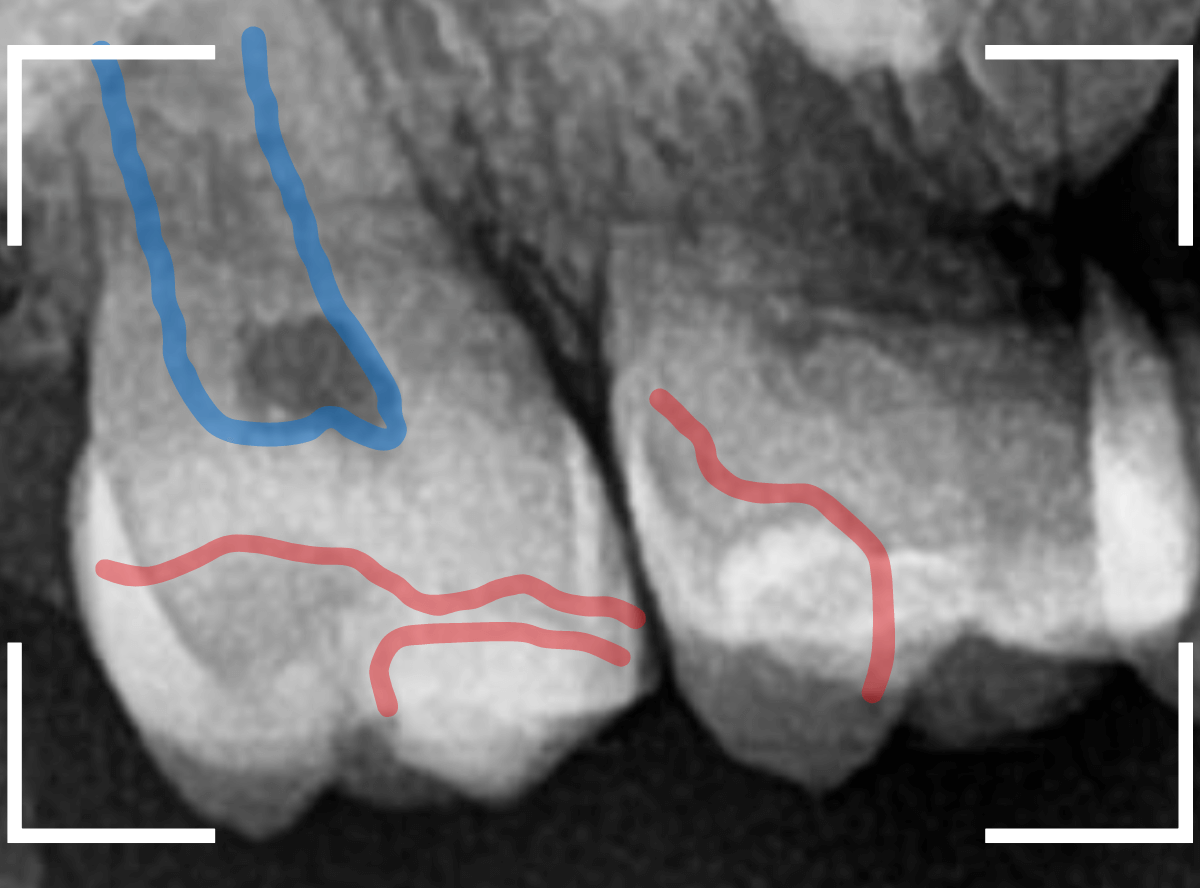

レントゲン写真で確認します。

青いラインが歯の神経、赤いラインが虫歯です。

歯の奥の見えない部分から、大きな虫歯になっているのがわかります。

神経を除去しなければいけないかもしれないくらいの虫歯です。